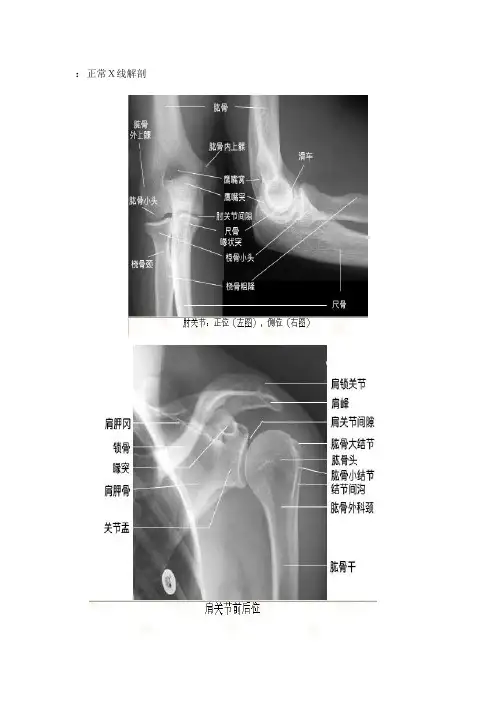

正常上肢X线解剖——肩关节平片前后位

正常上肢X线解剖——肘关节平片正、侧位